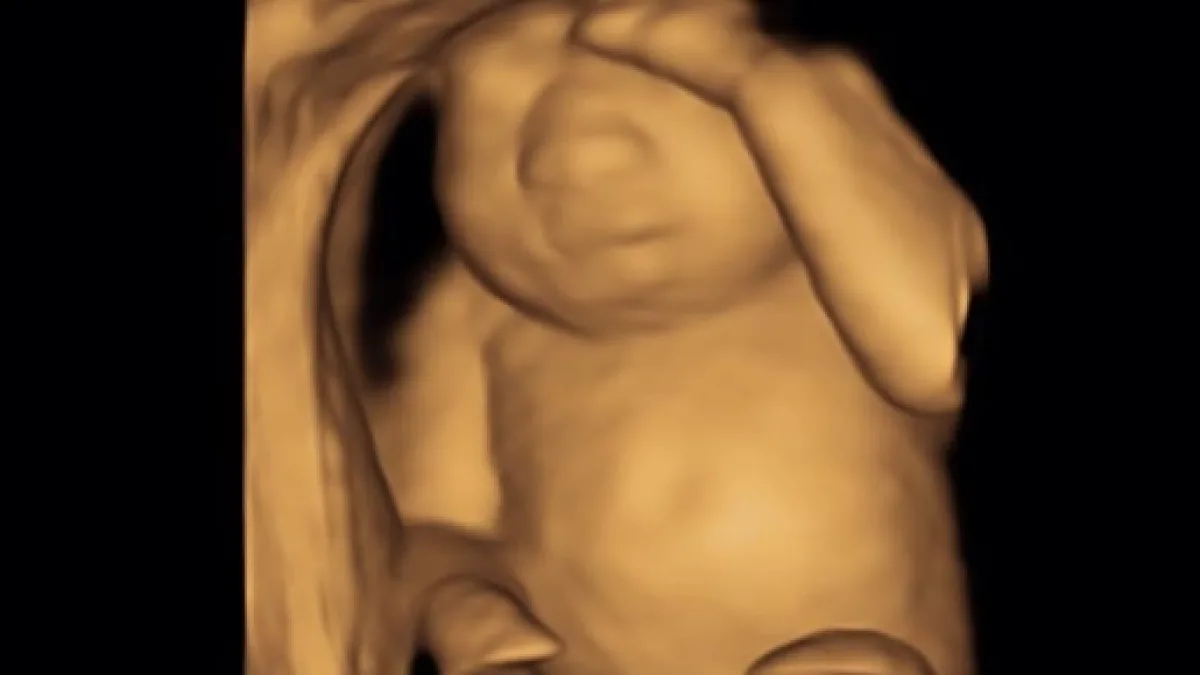

È il 13 dicembre quando Keri, postando su Facebook l’immagine dell’ecografia della sua bambina, decide di condividere il dolore pubblicamente e racconta: "Questo è il cuore perfetto di nostra figlia. Ha dei piedi perfetti e mani perfette. Lei è perfetta, reni, polmoni e fegato perfetti. Purtroppo, non ha un cervello perfetto. Abbiamo scoperto recentemente che è affetta da anencefalia ed è terminale. Di fronte alla terribile opzione di interrompere la gravidanza, abbiamo deciso di portarla a termine, così Eva, che significa letteralmente vita, potrà crescere forte e dare vita a più persone attraverso la donazione dei suoi organi. Non è stata una decisione facile. Per le prossime 20 settimane sentirò i suoi calci, il singhiozzo e saremo in grado di sentire il suo cuore perfetto battere, sapendo che staremo con lei solo poche ore quando nascerà.